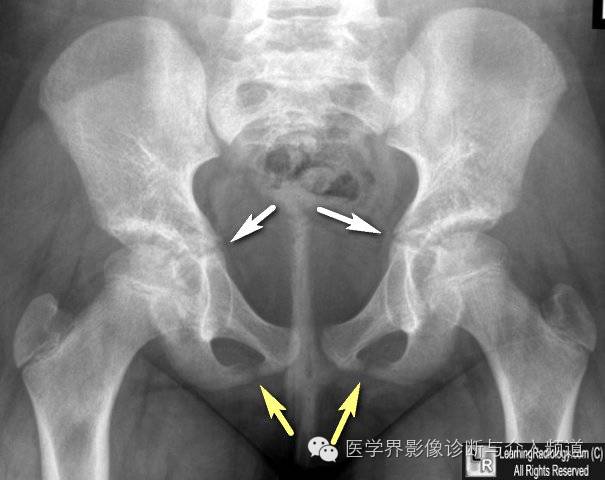

15、骨盆的软骨连接:骨盆由髂骨、坐骨和耻骨构成,未形成骨性连接之前表现为透亮线。